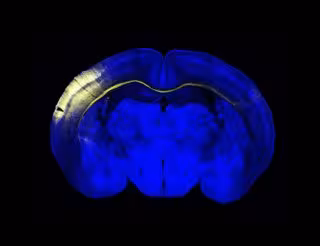

Sección horizontal del cerebro del ratón. Un grupo de neuronas de la corteza iluminadas en amarillo extienden sus axones a través del cuerpo calloso para conectar con el hemisferio contralateral.

Sección horizontal del cerebro del ratón. Un grupo de neuronas de la corteza iluminadas en amarillo extienden sus axones a través del cuerpo calloso para conectar con el hemisferio contralateral. - CNB/ CSIC - Archivo